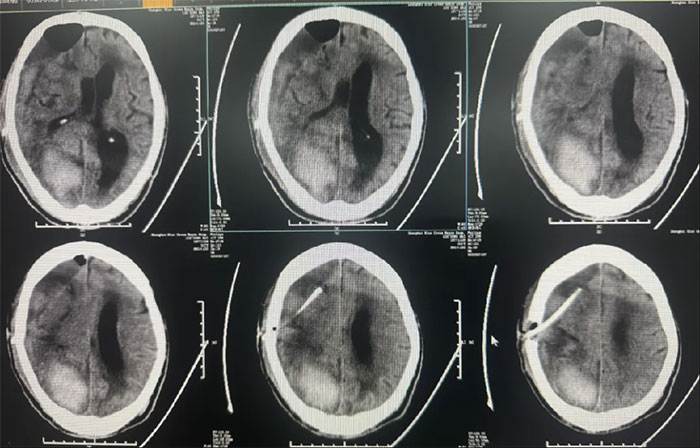

右顶枕叶出血,右侧额颞顶部亚急性硬膜下血肿,大脑镰下疝形成。

硬脑膜下钻孔引流术(长程引流管),引流管自右侧锁骨下皮肤穿出引流;

2025-02-18(发病后17天);

患者病情复杂,选择在局麻下进行,术程顺利。